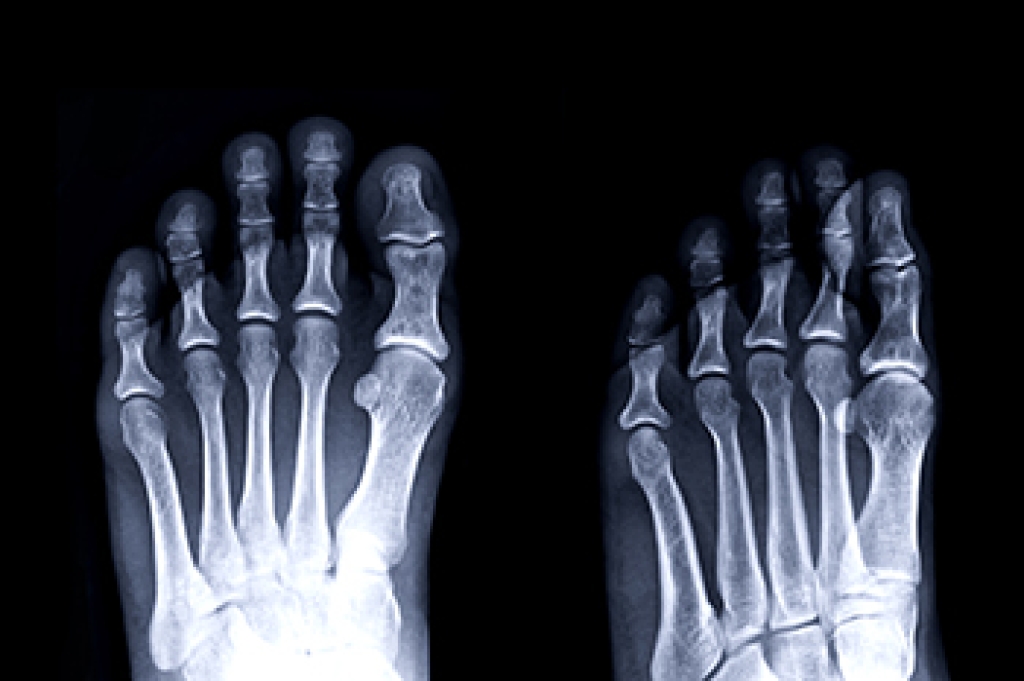

Arthritis is a joint disorder that involves the inflammation of different joints in your body, such as those in your feet. Arthritis is often caused by a degenerative joint disease and causes mild to severe pain in all affected areas. In addition to this, swelling and stiffness in the affected joints can also be a common symptom of arthritis.